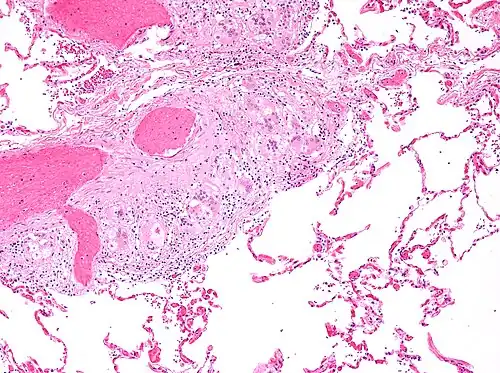

Histopathology

Sarcoidosis is characterized by the formation of non-necrotizing ("non-caseating") granulomas in various organs and tissues.[95] Giant cells, specifically Langhans giant cells, are often seen in sarcoidosis.[96] Schaumann bodies seen in sarcoidosis are calcium and protein inclusions inside of giant cells as part of a granuloma.[97] Asteroid bodies can be seen in sarcoidosis.[97] Hamazaki–Wesenberg bodies can be seen in lymph nodes and more rarely in lung biopsies with sarcoidosis and are inclusion bodies of lysosomes with protein, glycoprotein and iron.[98]

Sarcoidosis in a lymph node -

Pulmonary sarcoidosis with granulomas with Langhans giant cells and asteroid bodies -